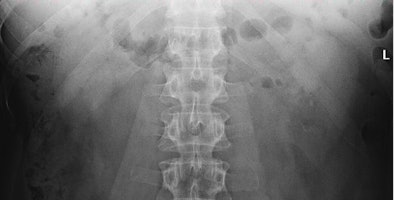

![]() |

| Two lithiasis in left kidney, seen on both techniques but much clearer on the tomosynthesis image (above), as well as nice visualization of the contour of the kidney. Images courtesy of Dr. Koen Mermuys. |